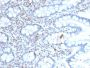

293T, NIH3T3, HeLa or Jurkat cells. Colon Carcinoma.

IHC, FFPE (verified)|WB (verified)

IHC (FFPE) (verified)|WB (verified)